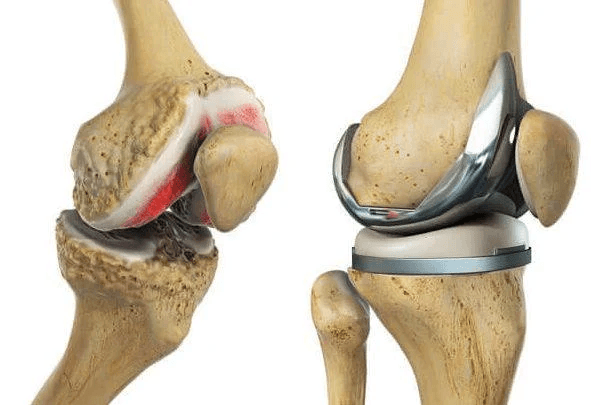

Capetele celor trei oase care formează articulația genunchiului sunt acoperite cu cartilaj articular, o substanță netedă și alunecoasă care protejează și amortizează oasele în timpul flexiei și extensiei genunchiului.

În această formă de artroză, cartilajul din articulația genunchiului se degradează treptat. Pe măsură ce se tocește, devine aspru și deteriorat, iar spațiul de protecție dintre oase se reduce. Acest lucru poate duce la frecarea os pe os și la apariția osteofitelor (ciocuri osoase).

- Proteza totală sau parțială de genunchi: înlocuirea suprafețelor articulare deteriorate